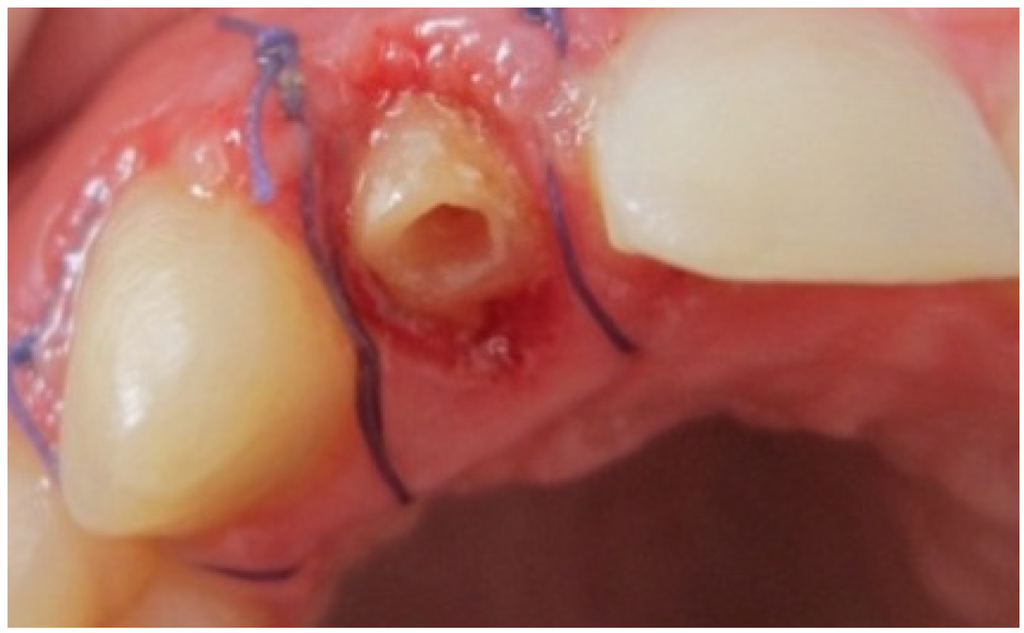

The margin level of the lateral incisor was planned to be 1 mm coronal to the central incisor. The waxed cast served as a guide for provisional restoration which had been optimized after the periodontal therapy until the objectives desired in the final restoration were achieved. The old crown was removed and the remaining tooth structure was evaluated as sound. Radiological reevaluation showed an adequate distance between the bone crest and the residual dental tissue (>3 mm) including biological width (Figure 3).

Figure 3. Radiological reevaluation showing the distance between crestal bone and inter proximal preparation level.